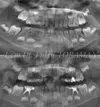

ولدت فوليا تورامان في إسطنبول عام 1991، وأكملت تعليمها الثانوي في مدرسة بيشكتاش ساكيب سابانجي الأناضولية. وتخرجت من كلية طب الأسنان بجامعة إسطنبول في عام 2015، حيث بدأت دراستها الجامعية. وأكملت بنجاح دراستها التخصصية في قسم طب أسنان الأطفال بكلية طب الأسنان في جامعة زونغولداك بولنت أجاويد في عام 2019، من خلال أطروحتها بعنوان "تأثير تنظيف الأسنان بالفرشاة على احتباس حشوات الانسدادات المختلفة".

تسوس الأسنان

نقص الأسنان

أمراض الأسنان واللثة